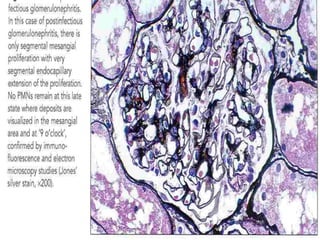

• Immunofluorescence microscopy

• Immunofluorescence (IF) microscopy reveals a

characteristic pattern of deposits of immunoglobulin

(IgG) and C3 distributed in a diffuse granular pattern

within the mesangium, and glomerular capillary walls.

• Other immune reactants (eg, IgM, IgA, fibrin, and other

complement components) may also be detected.

Coarse granular staining for IgG & C3 can be detected

in GCW

IgM→ less frequently

IgA & C1 & C4 → absent

Garland , starry sky & mesangial patterns